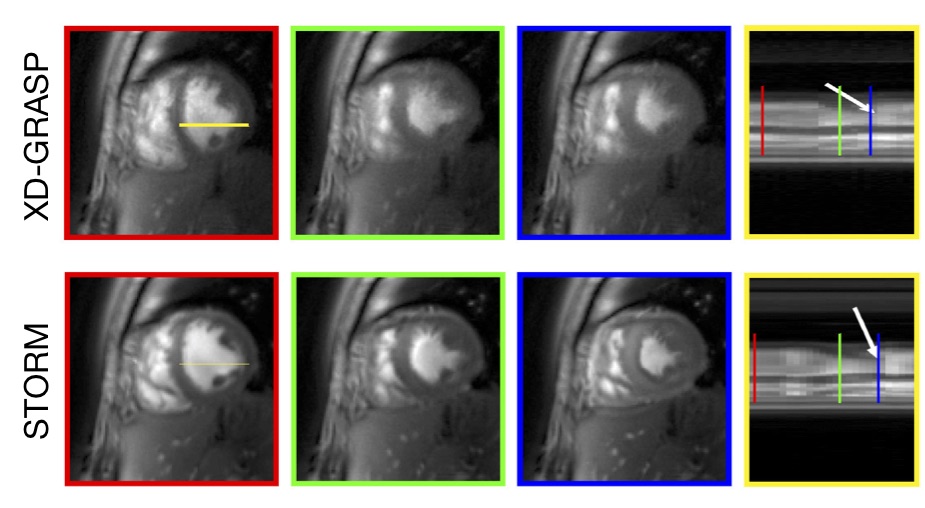

Refer to caption

(a) Comparison with XD-GRASP

(b) Comparison with breath-held cine

Figure 8: Illustration of SToRM algorithm [21] described in Section VIII-E. The SToRM algorithm exploits the manifold structure of free-breathing and ungated images in high-dimensional space. Specifically, each image can be viewed as a smooth function of two parameters: the cardiac phase and the respiratory phase. A non-linear transformation specified by (33) transforms the data to a subspace. We recover the images from their undersampled measurements by exploiting this structure, which is compactly captured by the nuclear norm of the feature matrix. We solve the optimization problem using an IRLS algorithm that uses the kernel trick, which eliminates the need to explicitly evaluate the complex features. (a) shows the comparisons of SToRM reconstructed images with XD-GRASP, which is an explicit binning strategy; XD-GRASP bin the images to distinct cardiac/respiratory phases, followed by the total variation recovery of the images. We observe that the implicit binning of the data offered by SToRM results in reduced blurring and improved fidelity (b) shows the comparisons of SToRM reconstructions (bottom row) with classical breath-held acquisitions (top-row) that bins the data from different cardiac cycles. We observe that the image quality is comparable, whole SToRM offers real-time imaging capabilities, allowing us to visualize cardiac and respiratory functions simultaneously. (a) Comparison